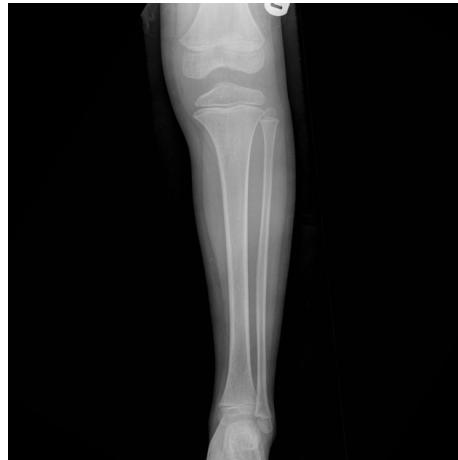

X-ray ap lat closed ,distal tibia extra-articular fracture, complete (two cortex), no articulation involvement, spiral (if two views appear broken), oblique (if one view) Oblique fracture, slight gapping (should be displaced if so), cortex appear normal, minimally displacement, angulation, rotation.